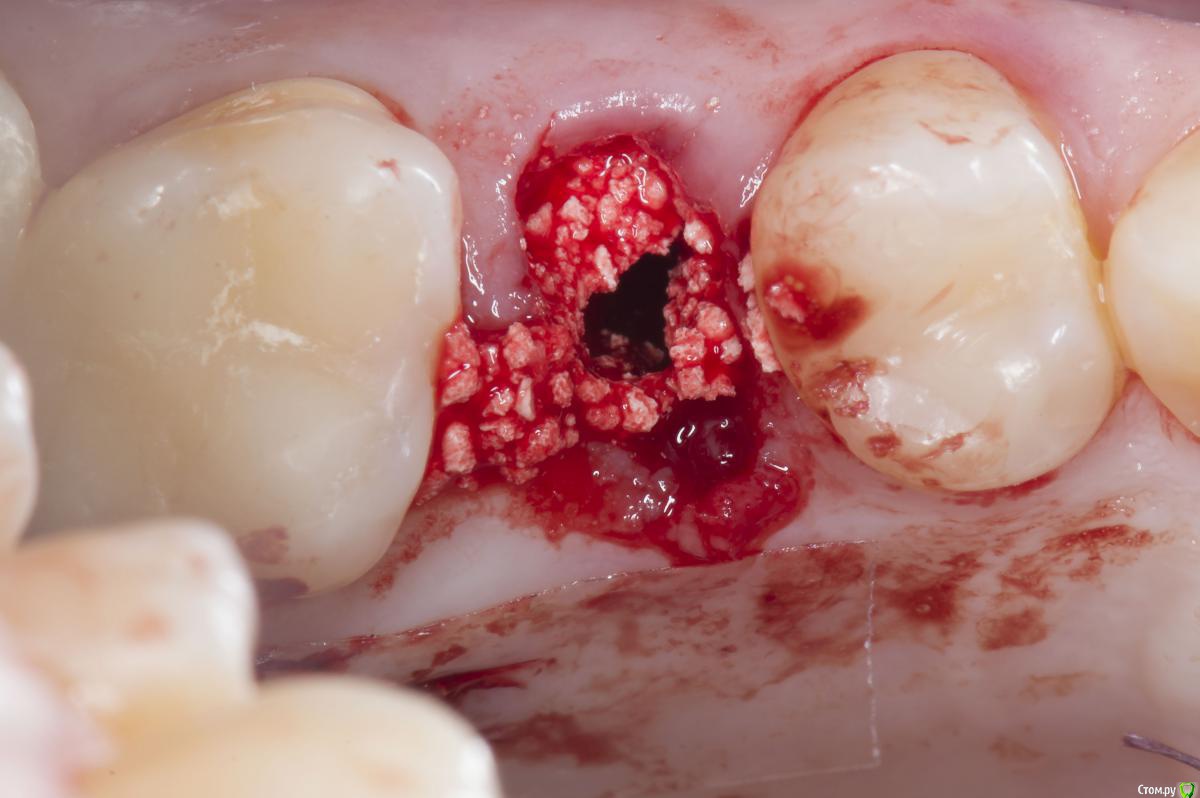

Sampson Опубликовано 10 августа, 2018 Поделиться Опубликовано 10 августа, 2018 (изменено) Очень мило для первого раза.. Здравствуйте коллеги.Сегодня поставил первый свой одномоментныйИзначальная картинаУдалениеСверление и контрольГрафтБолтКТФдмP.S. еще сдт взял с неба и вестибулярно подшил. А с неба заложил prf. Изменено 10 августа, 2018 пользователем Sampson 7 Ссылка на комментарий

Aquarius Опубликовано 10 августа, 2018 Поделиться Опубликовано 10 августа, 2018 Хорошая работа. Только куда графт делся после 3D заполнения? Отсосом забрали? витки импланта видны в лунке, а на предыдущем фото графт есть 1 Ссылка на комментарий